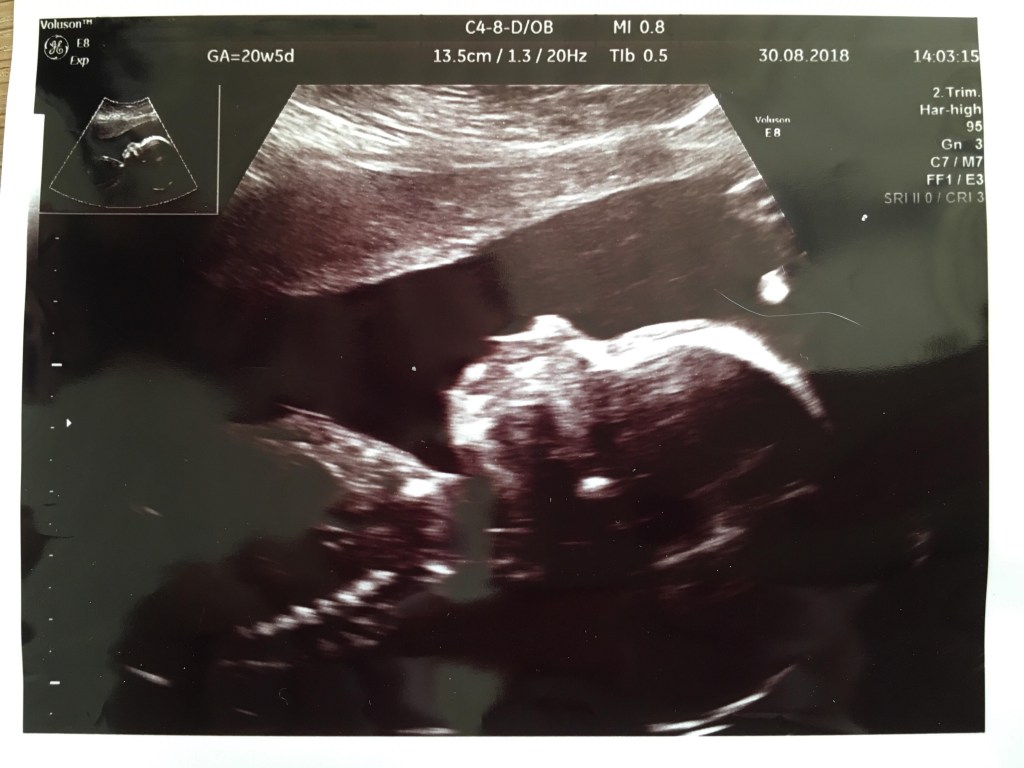

Jeg var meget utålmodig og ville gerne se min lille baby og dens hjerteblink. Martin var derimod mere rolig. Heldigvis fik jeg ham overtalt til at vi fik en såkaldt “tryghedsscanning” i uge 9 på en privat klinik. Jeg kunne simpelthen ikke vente længere. Jeg måtte bare vide at alt var godt. Eller om alt var godt..

Vi kom ind gennem en meget gammel port på Gothersgade. De gamle små mørkebrune trætrin knirkede under os, da vi langsomt gik op mod klinikkens dør. Martin gik forrest og en smilende kvinde tog imod os, da vi kom ind. En anden kvinde styrtede rundt og spurgte på vejen ind i et rum, om det var mig der var Elisabeth. Jeg nikkede og hun sagde “To minutter, så skal jeg være der”. Hun var inde i rummet et stykke tid, kom ud igen, smilede til os, mens hun hastigt hentede en stor vase med blomster, som hun satte ind i rummet. “Nu kan I bare komme ind” sagde hun. Vi trådte ind og der var meget større end jeg havde forventet. I den ene side stod en stor briks. Ved siden af var der placeret en stor indbydende lænestol med en pude i. Blomsterne i vasen stod på et bord op ad de gamle sprossede vinduer, og da kvinden så at jeg kiggede på dem, smilede hun og sagde “Ja, det går jo ikke at her ikke er hyggeligt, når I skal se jeres baby for første gang”. Det føltes som om at de begge kendte os i forvejen og nærmest havde glædet sig til, eller ligefrem ventet på, at vi skulle komme ind på deres klinik.

Selvom det var første gang jeg nogensinde skulle have en ultralydsscanning og se et barn i min mave, føltes det som det mest naturlige i verden. Jeg lagde mig til rette på briksen, trak lidt ned i mine cowboybukser og Martin satte sig i den store lænestol ved siden af og tog min hånd. For enden af briksen var en stor skærm, hvor vi kunne følge med i scanningen. Hun advarede mig om det kolde gele og smurte min mave forsigtigt ind, inden hun satte scanneren på. Og lige dér lå vores lille vidunder. Den lillebitte baby lå på siden med ryggen mod os, så vi kunne se den søde numse og de små ben, som han havde trukket op under sig. (På det tidspunkt vidste vi selvfølgelig intet om at det var en lille dreng der lå derinde og moonede til os).

I 10 minutter holdt vi i hånden og kiggede bare på en kidneybønne, der boblede rundt. En kidneybønne, der dengang var 9+4 uger gammel. Da vi var færdige tørrede hun geléen af min mave med et lille varmt håndklæde. Hun trykkede os begge i hånden og sagde tillykke med vores fine lille baby, før hun forlod rummet og gav os god tid til at samle vores ting.

Da vi kom ud til skranken lå en fin lyselilla mappe klar med dokumenter, der indeholdte al information fra scanningen. Der var målene på vores baby, mit navn og cpr-nummer og nogle andre ting, som jeg ikke helt vidste hvad var. Der var også nogle postkort, men vigtigst af alt, var scanningsbillederne og et link, hvor vi kunne se en video af vores lille baby-Blob boble rundt i min mave. Den video så jeg på flere gange de næste mange uger, hver gang jeg savnede et glimt ind i maven.